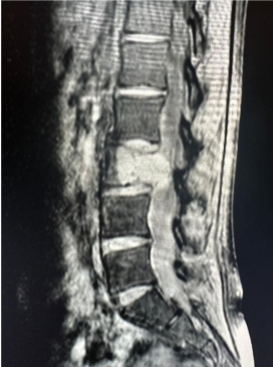

Common diagnostic tests include:

- X-rays (to assess spinal alignment and bending points)

- CT scans (for bony structures and abnormalities)

- MRI scans (to examine nerve and soft tissue damage)